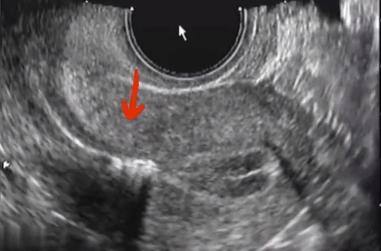

同时,移植管进到什么深度,医生也能很清楚地看到。医生也可以很明确的把胚胎移植到更为理想的着床位置。